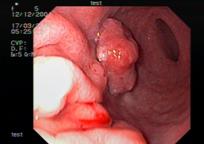

Распространенный рак желудка. Во II группе при визуальном осмотре 282 пациентов диагностирован распространенный рак желудка и согласно классификации указана его макроскопическая форма. У всех больных рак был подтвержден морфологически, причем дифференцированные аденокарциномы были у ,9%) пациентов, низкодифференцированные – у ,1%).Общий эндосонографический критерий всех форм распространенного РЖ – это наличие неоднородного гипоэхогенного образования, которое исходит из слизистой оболочки, с глубиной инвазии в мышечный или серозный слой, или выходит за пределы стенки желудка, с нарушением дифференцировки между слоями (рис.2).

Рис.2. 71 год. Блюдцеобразный рак нижней трети тела желудка.

Гистология – умереннодифференцированная аденокарцинома:

а - визуальная картина блюдцеобразного рака; б - эндосонограмма блюдцеобразного рака, гипоэхогенное образование с инвазией в серозную оболочку.